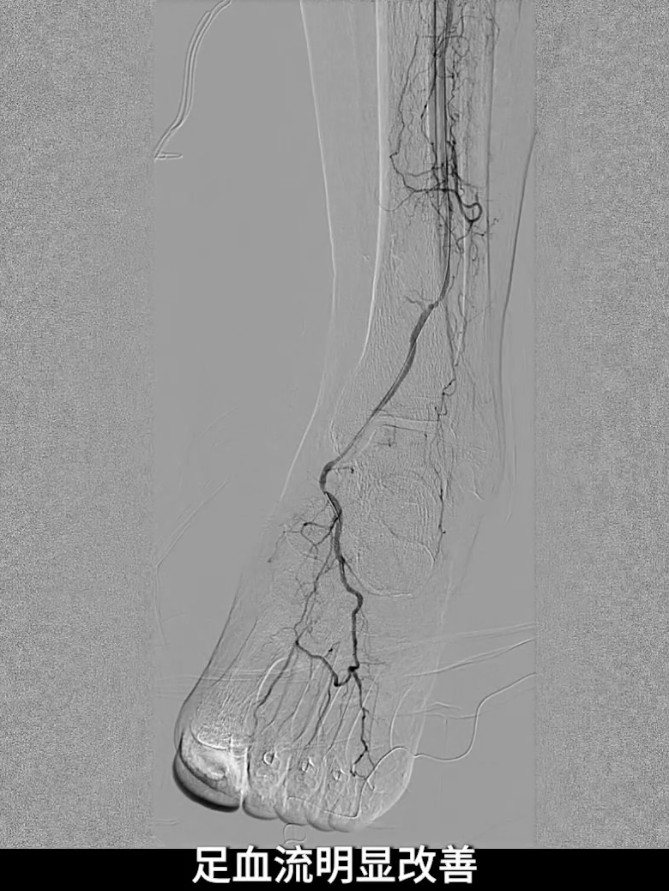

术后造影验证:股浅动脉管腔恢复通畅,无明显残余狭窄,局限夹层未对血流造成影响,无需植入补救性支架;膝下腓动脉流出道通畅,胫后动脉至足底动脉血流连续,足部血流灌注显著改善。